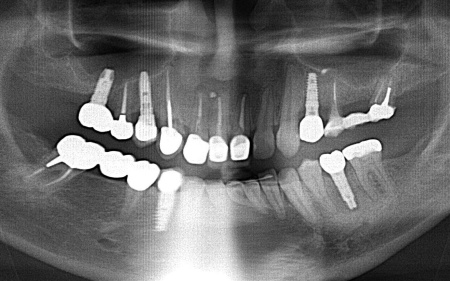

レントゲン撮影をして痛みの原因を詳しく検査したところ、左上下奥歯の歯根が割れており、その影響で痛みが出ていると考えられました。

しかし、レントゲン検査だけでは確実に歯根が割れているかどうかを確定することができません。

以上のことから、温存が難しいと判明している左上奥歯は抜き、左下奥歯は被せ物を取り外して内部を確認したうえで、適切な処置を行うことが望ましいと診断しました。

患者様は、以前当院で人工歯根を顎の骨に埋入して歯を装着するインプラント治療を受けていたため、今回も左上下奥歯ともインプラント治療を希望されています。

続いてインプラント手術を実施し、インプラントを正しい位置と角度で顎の骨に埋め込みました。